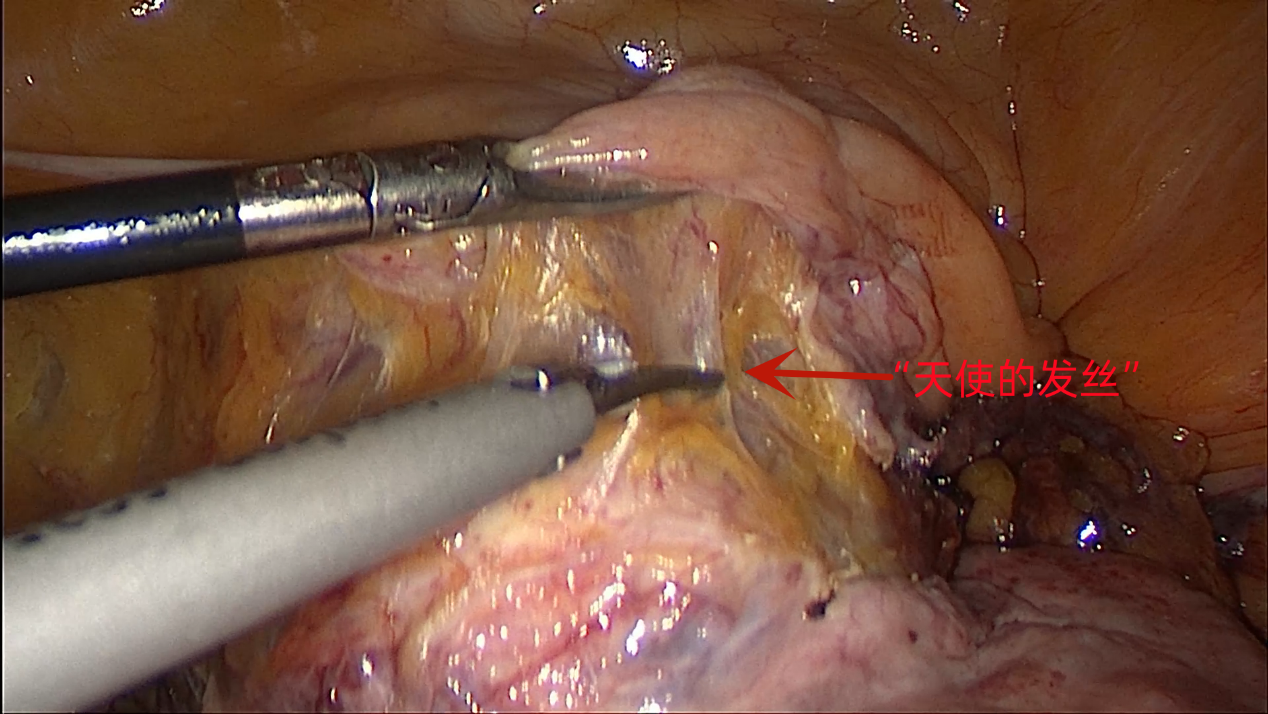

3.3 下推膀胱时,左手大把钳夹腹膜及膀胱组织,用力上提,这样可减少膀胱撕扯伤,且更容易看到“天使的发丝”,即膀胱与宫颈之间的潜在间隙;不停改变钳夹的位置,以保证足够的张力,超声刀边分离边切开。下推膀胱至举宫杯缘以下2cm左右,以便后期有足够的距离缝合阴道残端。(图10)

图10